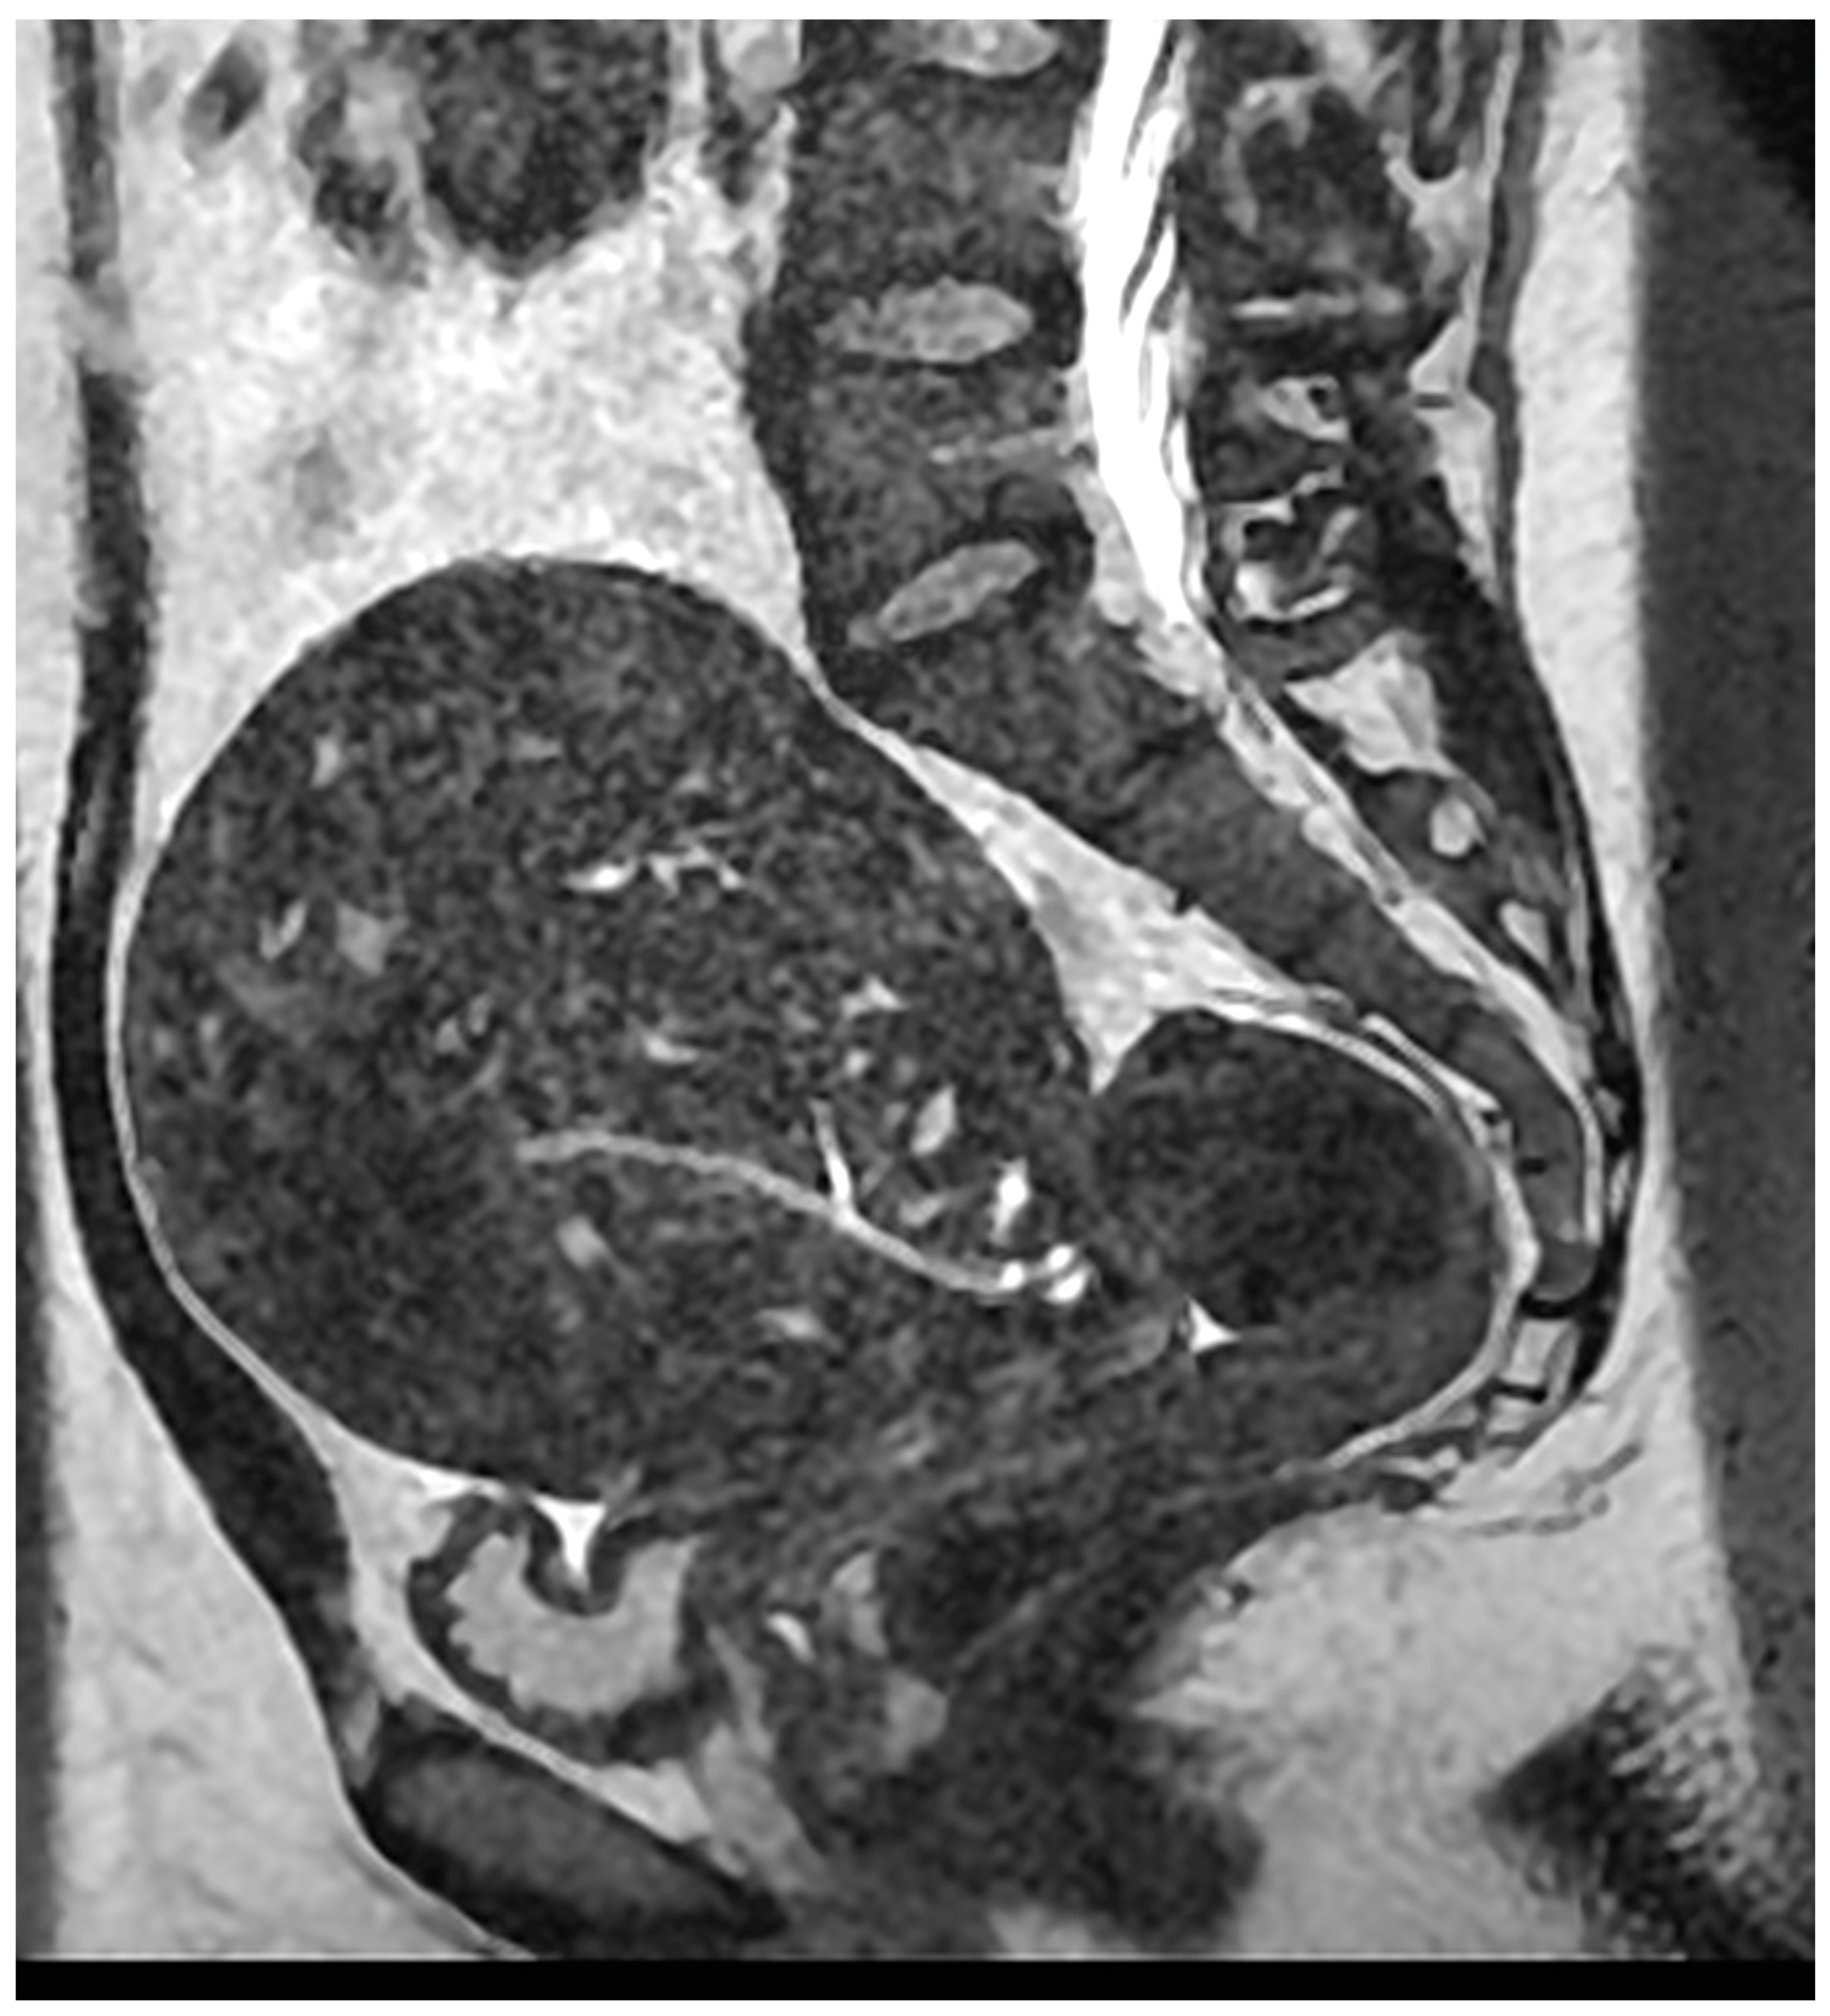

- Magnetic resonance imaging (MRI)